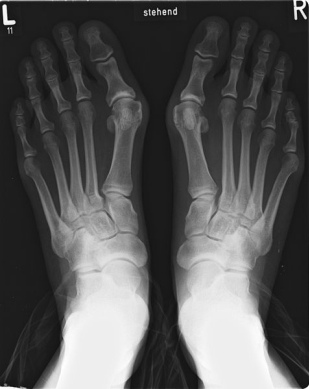

Die Fussverstümmelung eines

Spreizfuss mit Schiefzehe (Hallux

valgus), hier an einem Röntgenfoto

sichtbar Die Fussverstümmelung eines Spreizfuss mit Schiefzehe (Hallux valgus), hier an einem Röntgenfoto sichtbar [web9] [Foto 28]